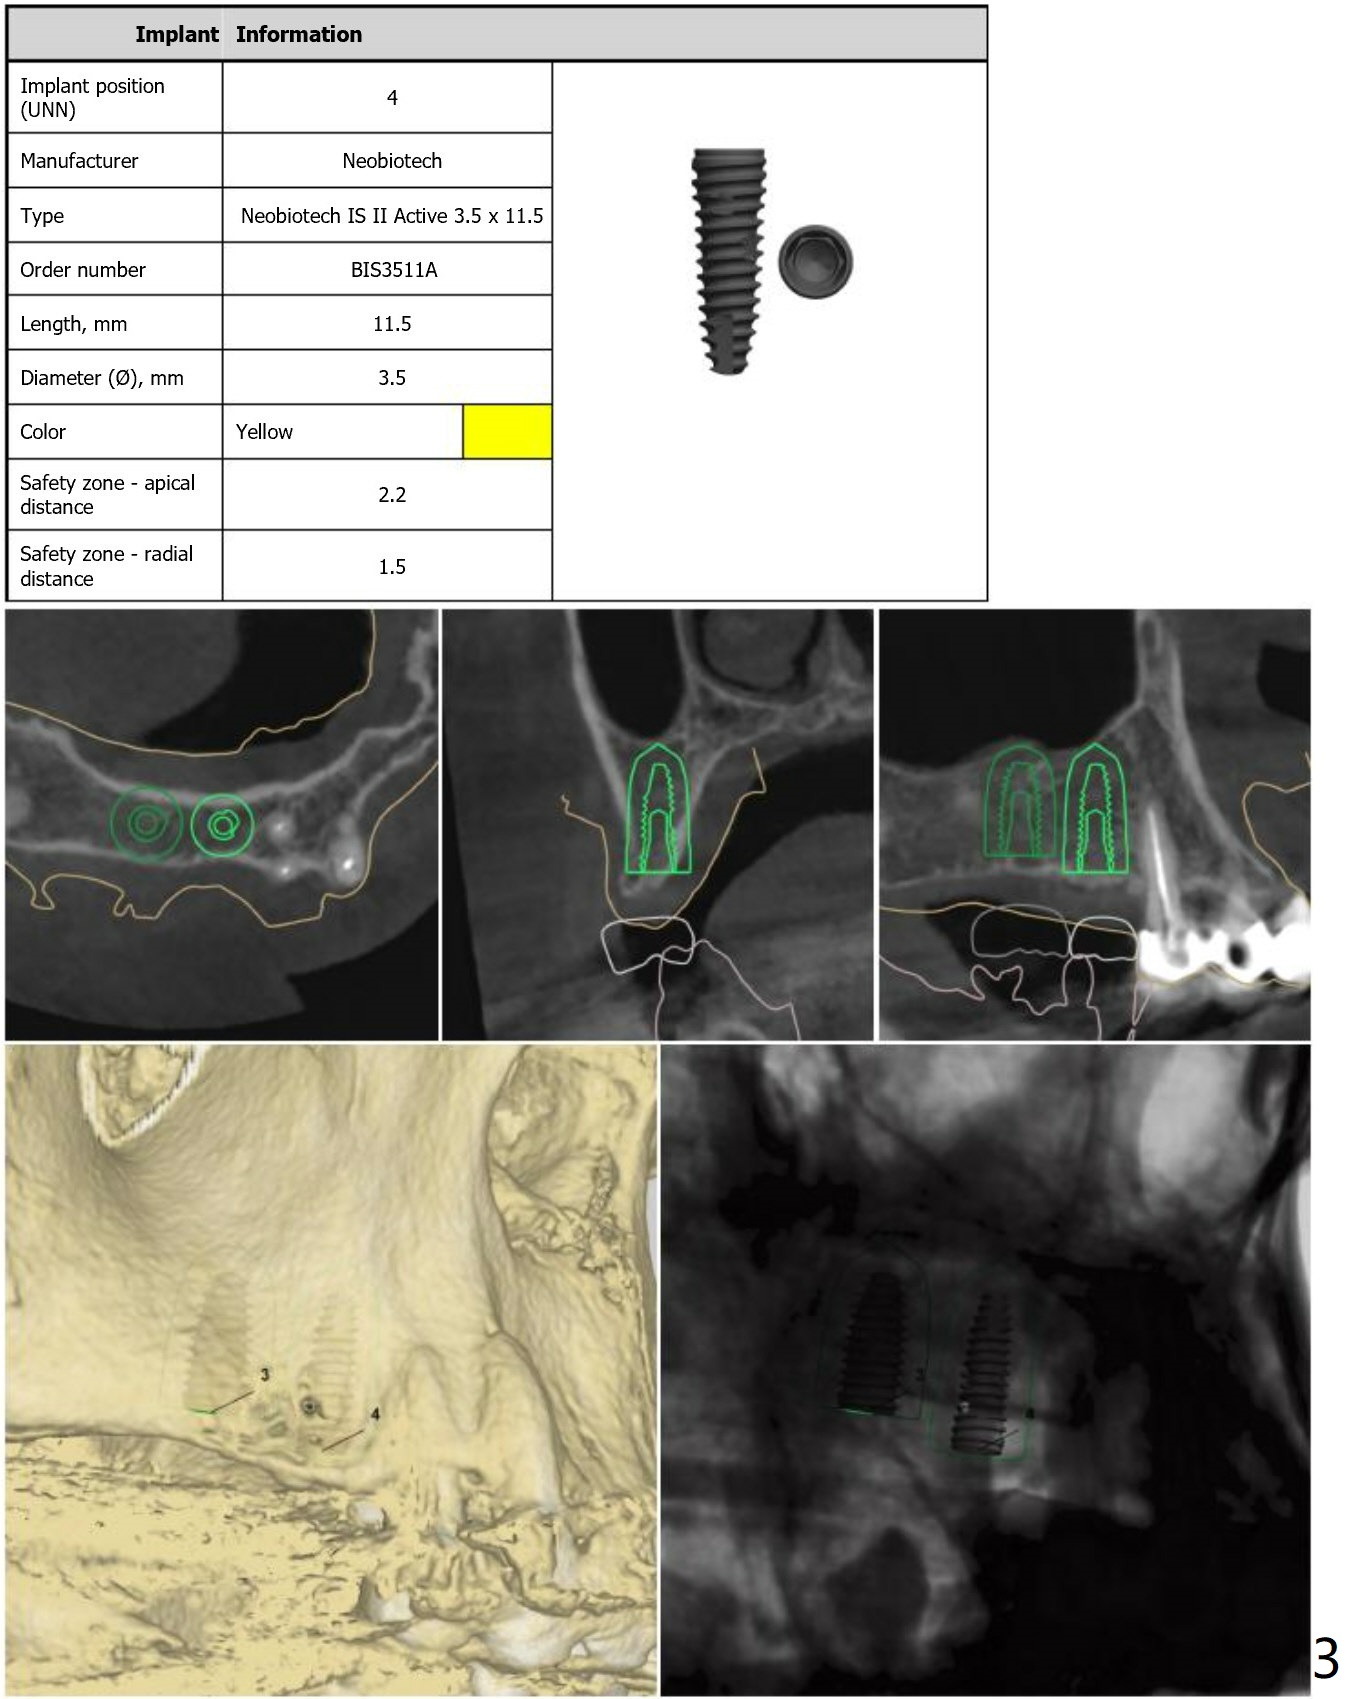

No Tap

Return to Upper Molar Premolar Immediate Implant, Trajectory